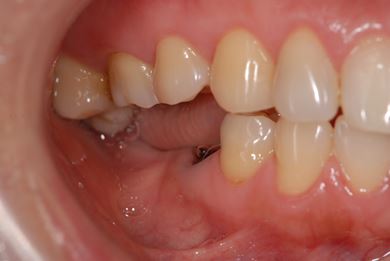

インプラントの症例写真 IMPLANT

インプラント治療+セラミック治療

| 主訴 | 前歯や、下の奥など、何本か気になる歯がある。 | ||||||||||||||||||||||||||||||||

| 治療方針 | インプラント治療により、機能的・審美的回復を行う。 | ||||||||||||||||||||||||||||||||

| 治療内容 | インプラント2本、メタルボンドセラミッククラウン4本、ジルコニアフレームオールセラミッククラウン1本(オールセラミック用土台1本) | ||||||||||||||||||||||||||||||||